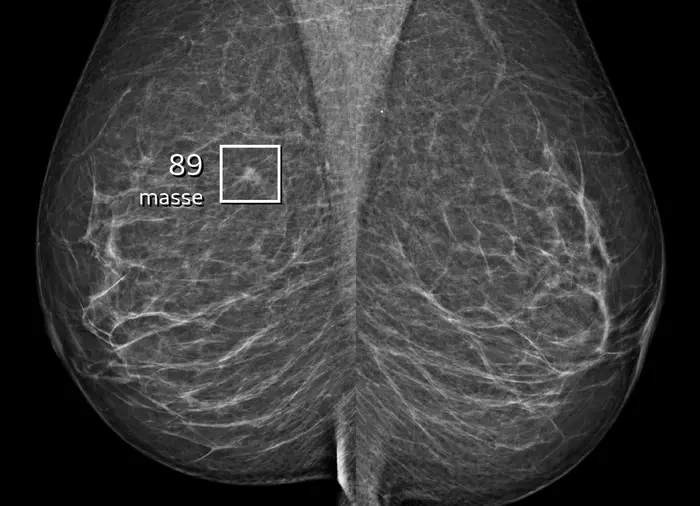

Can artificial intelligence be used to help detect breast cancer? The answer is an unequivocal 'yes' according to a new study from the University of Copenhagen’s Department of Computer Science and the Capital Region of Denmark’s breast cancer screening programme.

The study, an evaluation of the region's deployment of AI over nearly three years, demonstrates that the synergy between expert breast radiologists and the AI system results in significantly more cases of breast cancer being detected and the number of false positive results being reduced.

Prior to the introduction of AI, radiologists detected an average of 70 cases of breast cancer in every 10,000 screenings. Since being implemented, AI has allowed radiologists to find 82 women with breast cancer out of every 10,000, an increase of 12 cases per 10,000 screenings.

In addition to the fact that more cases of breast cancer were detected by the combination of radiologists and AI, a larger proportion of the cases involved small invasive tumours of one centimetre or less. The proportion of small tumours detected with the help of AI was 44.93 per cent compared to 36.60 per cent prior to the introduction of AI – a major bonus for the treatment of these women.

The remaining 30 percent of mammograms go through an independent double reading by two radiologists who can then use the AI system as a tool to automatically hone in on any suspicious lesions on the X-rays. Consequently, all examinations are assessed by at least one experienced breast radiologist, and the final result is always decided by breast radiologists.